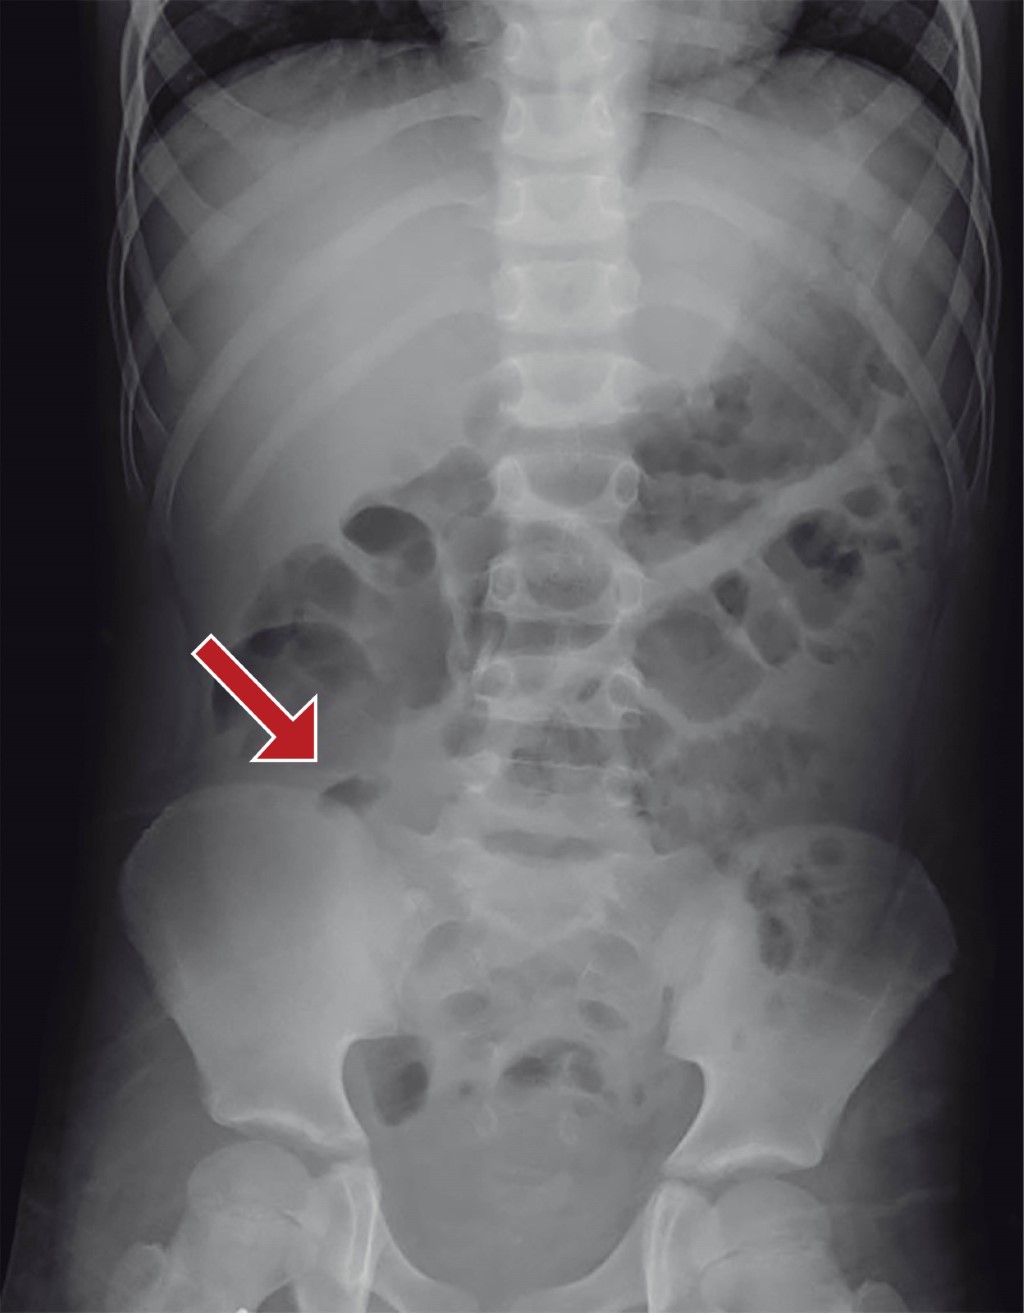

We report the case of a nine-year-old male with a history of having undergone surgery for acute appendicitis two and a half years before his current condition, which began 10 days before his admission and was characterized by generalized abdominal pain and vomiting on two occasions with gastro alimentary characteristics, managed by a physician with unspecified analgesics and without improvement. He continued with abdominal pain, predominantly in the right lower quadrant, accompanied by nausea and vomiting. For this reason, he went to the Emergency Department of the hospital, where the patient was found with pain in the right lower quadrant, in the trigger position, and with data of peritoneal irritation. Laboratory tests were requested, reporting a hemoglobin level of 13.0 mg/dl, hematocrit of 38.2%, 15.15 × 109 white blood cells, and 76.4% neutrophils. The plain abdominal X-ray showed a fixed loop image in the right iliac fossa (Figure 1). An abdominal ultrasound was requested, which reported a collection of 5 × 4 cm (Figure 2), so the General Surgery Service was consulted since there was no pediatric surgeon on shift; 24 hours after admission, the patient was evaluated by surgery, finding the patient with discrete voluntary resistance in the right lower quadrant and peritoneal irritation. An abdominal MRI was requested to determine the probable etiology of the collection, which reported an amorphous collection in the right iliac fossa, with irregular and well-defined borders, measuring 5.1 × 4.3 × 4.9 cm in its longitudinal and transverse anteroposterior diameters, respectively, compatible with an abscess in the right iliac fossa.

Figure 1